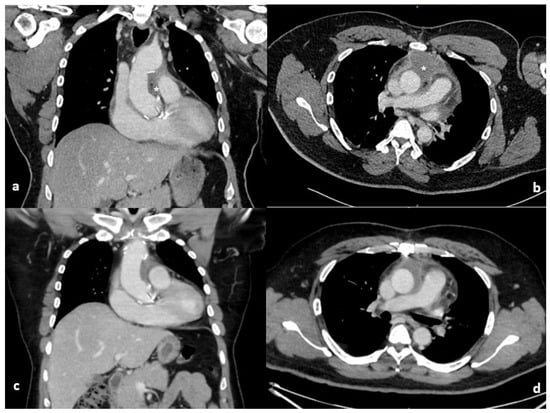

Postoperatively, inflammatory markers rose in keeping with a postoperative inflammatory response. C-reactive protein peaked on postoperative day 3 and subsequently demonstrated a sustained downward trend. White cell count peaked later, on postoperative day 8, but remained discordant with the patient’s clinical status, as he was afebrile, haemodynamically stable, and without features of sepsis. Serial blood cultures were negative. Table 1 demonstrates the timeline of inflammatory markers, imaging and management. This temporal dissociation between biochemical markers and clinical findings, together with radiological features and knowledge of intraoperative Surgicel® placement, supported a conservative management strategy. Empirical intravenous amoxicillin–clavulanate was commenced in response to rising inflammatory markers and later transitioned to oral therapy. All blood cultures obtained during this period were negative. An enhanced CT, Figure 1, revealed a 6.5 × 5.5 × 10 cm loculated collection with blebs of air and enhancing walls surrounding the ascending aorta, mainly within the aortopulmonary space. Given the stable clinical picture, the surgical correlation with the use of Surgicel® Fibrillar in this location, a decision was made to conservatively manage the patient on oral antibiotics for an additional week in the community. A repeat CT scan was arranged on the 27th postoperative day, which revealed the reduction in size of periaortic fluid collection and complete resolution of locules of gas. The inflammatory markers at this point were normalised with WCC and CRP of 9.03 × 109/L and 25.9 mg/L, respectively. Subsequent surveillance CT imaging at 6 months and 18 months postoperatively confirmed stable aortic graft appearances with no evidence of residual collection or infection.

Figure 1. Coronal and axial computed tomography of the chest on the 10th (a,b) and 27th (c,d) post operative days. The initial large loculated collection with blebs of air and enhancing walls (*) surrounding the ascending aorta has improved with conservative management on repeat imaging.